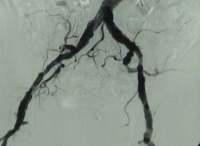

Filmbeispiel: TASC D → offene Rekonstruktion

AVK Stadium IV rechtes Bein, Stadium III linkes Bein mit:

- hochgradiger Arteriosklerose der terminalen Aorta und Beckenstrombahn bds.

- langstreckigem Verschluss der A. femoralis superficialis bds.

- Teilverschlüssen der Unterschenkelarterien bds.

Präoperative DSA des Patienten: